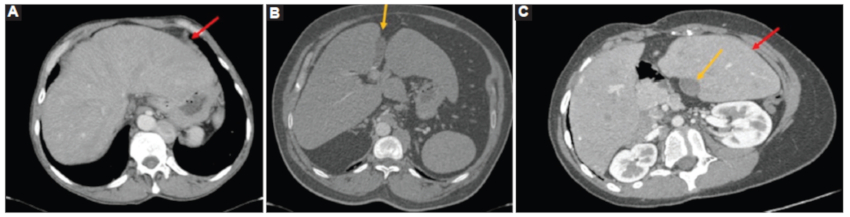

Pulmones y bronquios

El síndrome de heterotaxia con isomerismo izquierdo se asocia a pulmones simétricos, bilobulados con una única cisura, como se observó en los casos 1, 2 y 3 (Figs. 3 y 4).

Los bronquios fuente son largos bilateralmente y pasan por debajo de la arteria pulmonar correspondiente, comportándose ambos como bronquios fuente izquierdos. Presentan bifurcación anatómica izquierda (bronquio lobar superior e inferior) y la distancia entre la carina y la primera división del bronquio princial es igual en ambos pulmones.